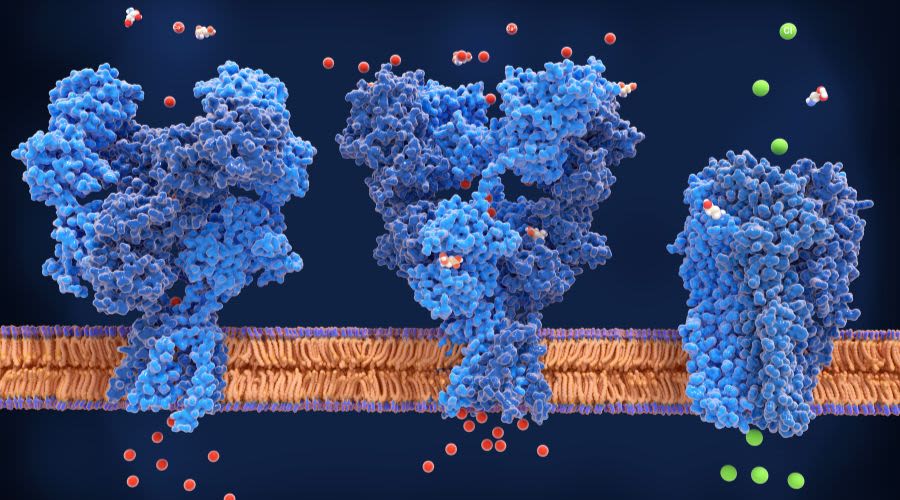

Tau protein is found to impair the ability of neurons to repair and remove mitochondrial waste